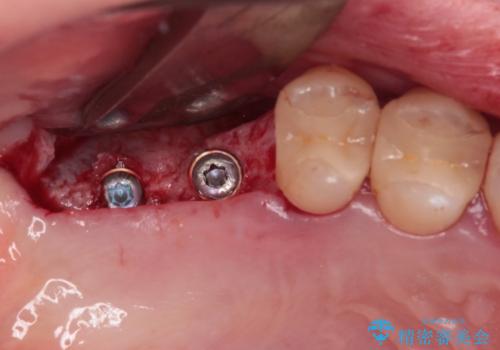

かかりつけ医では、歯周病治療は終了したため、抜歯を行った右上奥歯にインプラント埋入を行うとの案内があったそうです。

検査を行ったところ、歯周外科処置や抜歯が必要と思われる箇所が散見されたため、あらためて当院に歯周病の初期治療から行うこととしました。

- 外科手術のため、術後に痛みや腫れ、違和感を伴います

- メンテナンスを怠ったり喫煙により、お口の中に大きな悪影響を及ぼすインプラント周囲炎等にかかる可能性があります